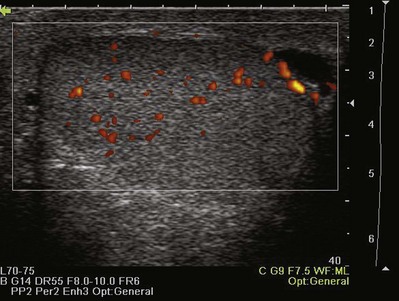

Color Doppler ultrasonography allows for evaluation of the velocity and direction of motion. A color map may be applied to direction with the most common assignation of the color blue to motion away from the transducer and red for motion toward the transducer. The velocity of motion is designated by the intensity of the color; thus the brighter the color is, the more rapid the motion. Color Doppler may be used to evaluate the presence of absence of blood flow in the kidney, testes, penis, and prostate. It also may be useful in the detection of ureteral “jets” of urine emerging from the ureteral orifices.

Power Doppler ultrasonography is a mode that assigns the amplitude of frequency change to a color map. This does not permit evaluation of velocity or direction of flow but is less affected by back-scattered waves and therefore a more sensitive mode for detecting blood flow. Power Doppler is less angle dependent than color Doppler and is three to five times as sensitive as color Doppler ultrasound for detecting flow.